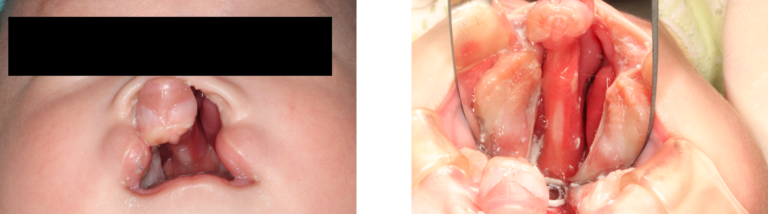

口唇口蓋裂症例

左側唇顎口蓋裂

年齢

生後3ヶ月男児

治療方針

PNAM

治療期間

3ヶ月

治療回数

12回

治療費

¥275,000(税込)

初診生後2ヶ月

治療2週間後

治療3ヶ月後